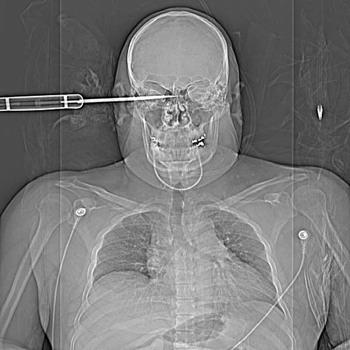

Şoke eden röntgen filmleri

Bu röntgen filmleri görenleri şaşkına çeviriyor!